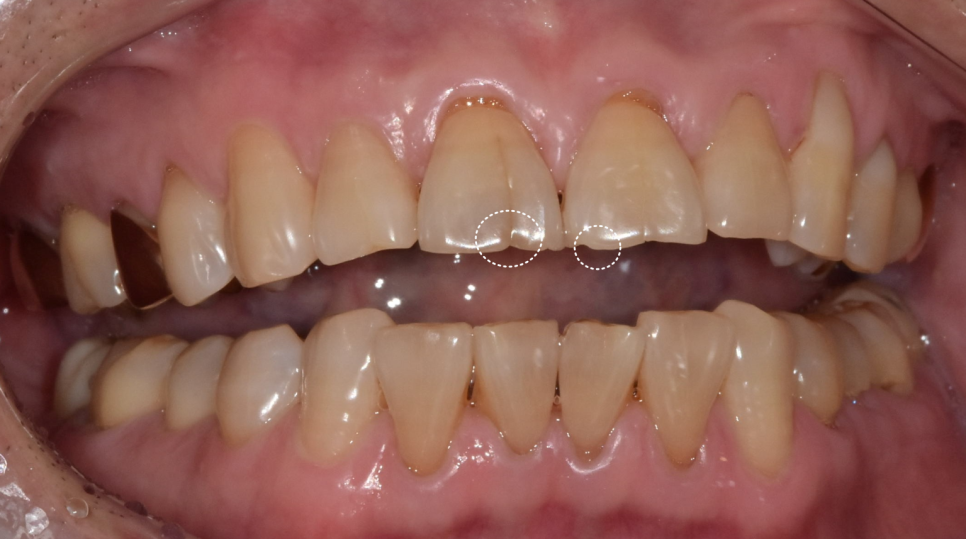

240605

보통은 위 앞니가 아래 앞니를 살짝 덮으면서,

가위처럼 음식을 잘라내는 구조를 이룹니다.

하지만 이 분은 위아래 앞니 끝과 끝이

정면으로 맞닿아 있었습니다.

식사할 때마다 마치 못 위에 망치를

계속 내리치듯, 앞니 끝끼리 정면으로 부딪히고 있었던 겁니다.

치아를 살펴보니 앞니 앞면 중앙에 금이 쭉 가 있었습니다.

치경부(치아와 잇몸 경계) 쪽엔 마모가 진행되어 뿌리 쪽이 파여있습니다.

특히 금이 더 깊게 간 오른쪽 앞니 통증을 호소하셨습니다.